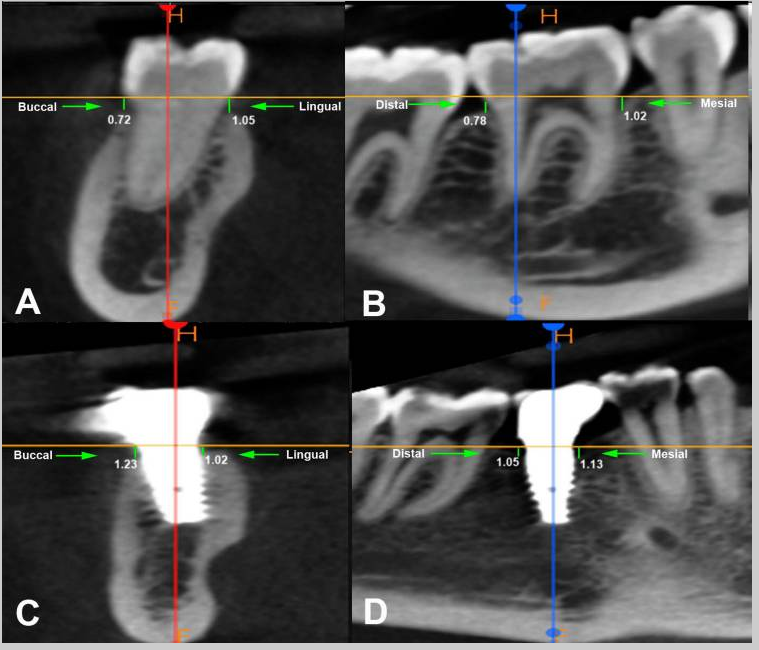

Case photos below provided by Rehberger Bescós F, Salgado Peralvo ÁO, Chamorro Petronacci CM, Chele D, Camacho Alonso F, Peñarrocha Oltra D, Lado Baleato Ó, Pérez Sayáns M. [Marginal bone loss and associated factors in immediate dental implants: a retrospective clinical study.](Marginal bone loss and associated factors in immediate dental implants: a retrospective clinical study - PMC)

Measurements for the calculation of the MBL performed: A Preoperative evaluation; B immediate postoperative period; C 2 months after placement of the implants; D 36 month follow-up

A BL example in IDI #33 (A1: March 2019- A2: September 2023); B BR example in IDI #26 (B1: November 2019- B2: January 2020); C BO example in IDI #46 (C1: January 2019-C2 January 2020)

This study concluded:

The present study supports the clinical efficacy of immediate implant placement protocol with high survival rates and acceptable MBL. Regarding the latter, the insertion of implants bone level about 3 mm infracrestal should be considered to ensure a subcrestal implant platform position during bone remodeling during the first months after implantation. The insertion of immediate implants in the jaw compared to the maxilla, the abutment height and rotational abutments demonstrated a positive impact over the MBL.